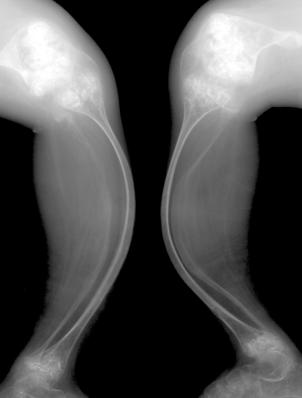

股骨头骨骺缺血性坏死:骨骺变小、碎裂变形,颈短粗,头向外移,内侧间隙增宽。

成人股骨头缺血性坏死:股骨头变形,增骨质生硬化囊变并存;左侧间隙变窄,右侧间隙正常。关节间隙变窄,退行性骨关节病,股骨头呈磨菇头状变形

好发部位:股骨头、胫骨结节、椎体骺板、腕舟月骨、足舟骨等。

病因:外伤、营养、解剖缺陷、代谢内分泌。

临床表现:局部疼痛,运动障碍。